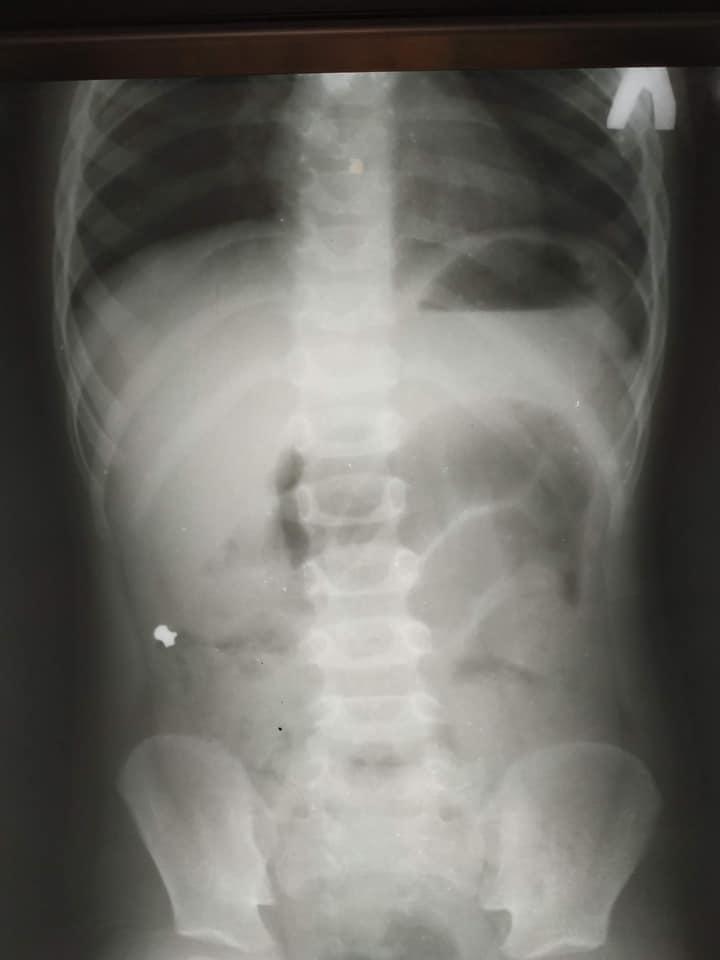

Дитячого хірурга Кирила Лапшина дуже здивував рентген-знімок. У черевній порожнині чітко візуалізувався дивний сторонній предмет, який за обрисами схожий на кулю від пневматичної гвинтівки. Медик уточнив у тата хлопчика, чи міг син проковтнути кулю.

Чоловік повідомив, що у них вдома є пневматична рушниця та до неї металеві кулі, якими дитина нещодавно гралася. Ймовірно, випадково хлопчик проковтнув одну з них.

Все б закінчилося добре, якби куля потрапила зі шлунка в кишківник і вийшла. Але в маленького пацієнта куля потрапила в апендикс, це стало причиною запального процесу, через що хлопчику знадобилася термінова операція. Хворому провели лапароскопічну операцію — видалили запалений апендикс через три невеликі проколи у животі. «Коли ми видаляли апендикс, я відразу побачив, що в ньому є потовщення. Ми його видалили й уже назовні розрізали.

Там справді була куля! Вона, як стороннє тіло, потрапила з кишківника в апендикс і створила його обструкцію. Це і стало незвичайною причиною апендициту», — повідомив дитячий хірург Кирило Лапшин. Малечу вже виписали додому, а його батько пообіцяв медикам надійно ховати кулі та зброю.